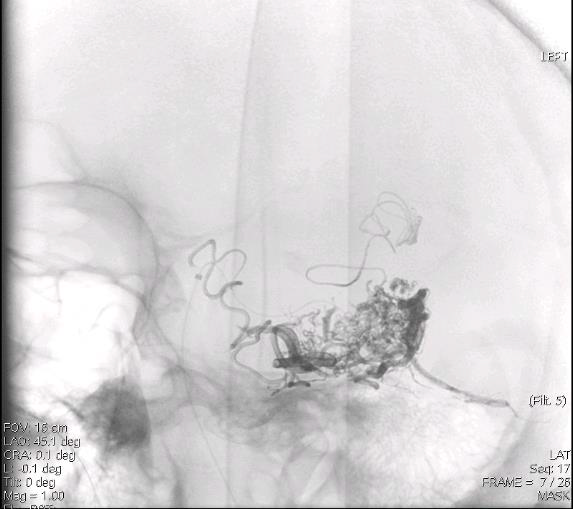

КЛЕЙ УЖЕ ИСПОЛЬЗУЕТСЯ ДЛЯ ЛЕЧЕНИЯ АВМ

ДОСТАВКА ЧЕРЕЗ МИКРОКАТЕТЕР

✱С разрешения д-ра Raabe R.

Большое количество клея / тромба

остаётся в АВМ, изображение МРТ

"Если мы можем склеить высокопоточные церебральные АВМ, почему бы не склеивать низкопоточные варикозные вены?"

Dr. Raabe R., 2008